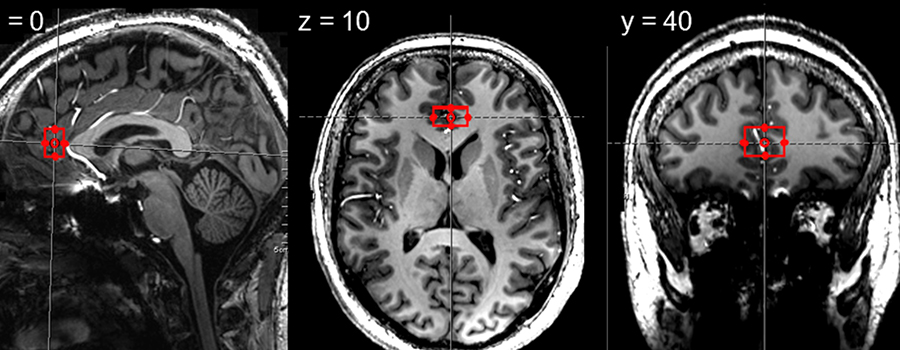

Illustration: Region called pregenual anterior cingulate cortex where we measured neurometabolites in healthy participants and in participants with major depressive disorder.